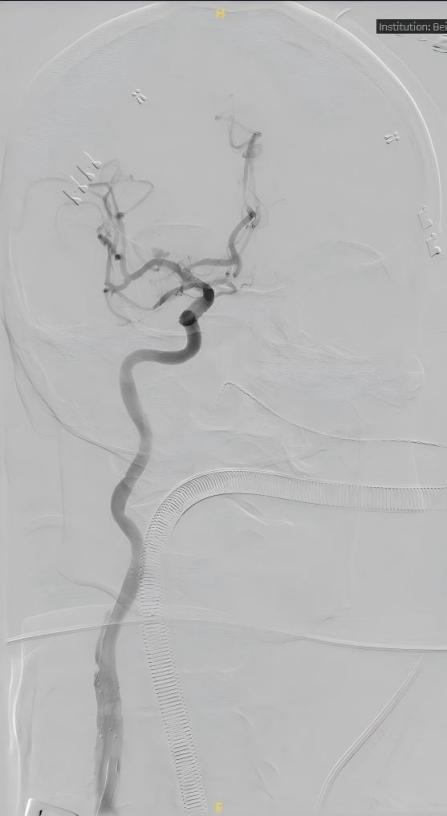

在麻醉团队的保障下,联合手术有序开展。血管外科吴巍巍团队率先实施颈动脉TCAR手术,解除了颈动脉斑块脱落导致脑梗的风险,为后续颅内动脉瘤的治疗建立通路;神经外科吕宪利团队接续操作,通过介入技术精准释放密网支架,重塑颅内血流、封闭动脉瘤,成功拆除颅内“不定时炸弹”,同时保护边支血管。

术后影像资料